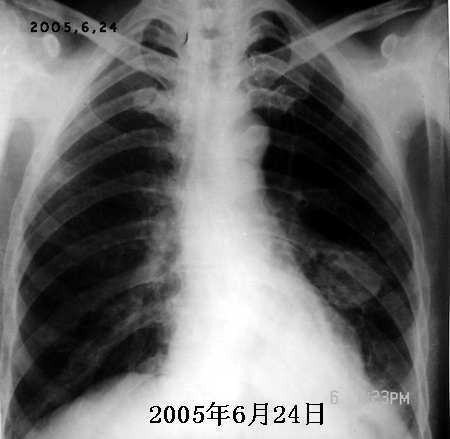

以下是引用jiajie在2005-11-6 22:07:00的发言:[br]1)左肺下叶阻塞性肺炎,胸腔积液,中心型肺癌可能大,建议纤支镜。[br]2)结合30年打石史,双肺弥漫性小结节考虑矽肺。

以下是引用sdqzwyx在2005-11-7 19:59:00的发言:[br]双肺弥漫大小不等的粟粒状结节影;肺纹理走行失去自然,粗细不均,边缘不规则,小叶间隔增厚;左上肺示不规则形致密影,从斑块边缘向周围伸出长短不一的致密索条影,临近的血管、支气管和叶间胸膜等结构受牵拉移位;左下肺示不规则团块状影,其内示空洞,洞内壁尚光整,左侧胸腔积液。右肺下叶背段亦示部分病灶融合。双肺可见局限性肺气肿。[br]诊断:结合病史符合三期矽肺表现(少数矽肺纤维斑块内可以形成空洞,一般认为是斑块中央感染引起坏死所致)但尘肺病人易合并肺结核,诊断可为三期+tb。所以此病人应进一步检查是否合并结核。